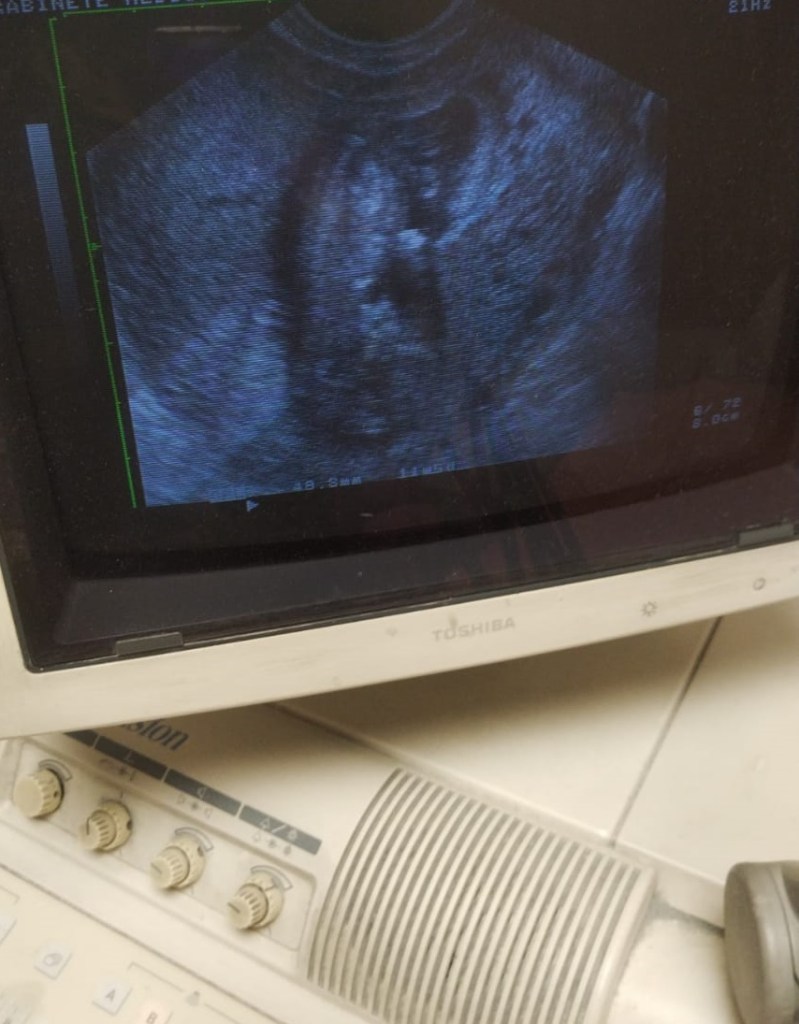

Anny esta andando despacio en las cercanías de un abortorio de Madrid al que los rescatadores Juan Pablo II llamamos «El Cementerio». Se acercan dos rescatadores. Ella les va preguntando. Les cuenta que tiene miedo que la echen del trabajo por estar embarazada. Trabaja todo el día. Es su primer hijo. Su pareja no tiene trabajo fijo. Va enumerando todas las situaciones que día a día tienen miles de mujeres. La policía pasa dos veces mientras que la pareja de rescatadores sigue hablando con ella. En un momento ella se calla y empieza a mirar al coche de policía que se para para mirar. Cuando la policía se va, ella les deja su teléfono. Pasan unos días y viene a la asociación MasFuturo con el padre del bebe que espera. Después de bastante tiempo empiezan a darse cuenta del milagro de ser padres. Se van contentos. El otro día se hizo su primera ecografía acompañada de María, una voluntaria de la asociación. No para de dar las gracias. Sabe que no va a olvidar que intentó abortar a su bebé. Pero tiene la oportunidad de dejar su testimonio con la foto de su bebé.